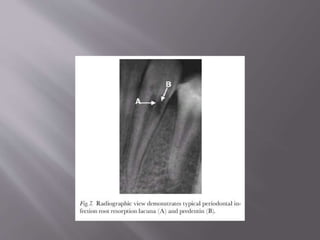

Radiographically,

 Single resorpton lacunae in the dentin usually

at the crestal bone level, especially to the

coronal and apical direction.

 Resorption progresses, radiolucency may be

observed at the alveolar bone adjacent to the

resorption lacunae of the dentin.

 Radiographic appearance

 resorptive process occurs mesially or distally on the root

surface

 Single resorption lacunae in the dentin usually at the crestal bone

level

 The radiolucency expands coronally and apically in the dentin,

and reaches, but usually does not perforate, the root canal

 irregular, diffuse radiolucency of nonuniform radio-density

(Makkes & van Velzen 1975).